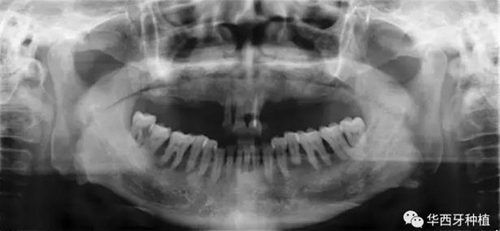

吳教授首先就全口牙缺失病種自身具有的特點,進行了總結。特別強調了嚴重的牙槽骨骨質萎縮,其結合上下頜骨的解剖結構(上頜竇,下齒槽神經(jīng)管)后導致的種植區(qū)骨量不足。

接下來吳教授分別針對幾種具有不同特征的病例,進行分析、設計與病例回顧。對于不同骨量缺失的全口牙缺失患者,可選的種植修復方式有較為傳統(tǒng)的組牙種植修復、種植覆蓋義齒修復、all-on-four或all-on-six的修復方式。拓寬了我們在全口牙缺失病例種植與修復治療中的視野與選擇。

對于骨量較好的患者,選擇設計與手術方法較為簡單的傳統(tǒng)的組牙種植修復,過程較為便捷,遠期效果穩(wěn)定。但是時間與經(jīng)濟成本高,并且在全口牙缺失患者口內,由于參照物較少,種植體的位置,共同就位與平行度的選擇與構建均存在一定難度。